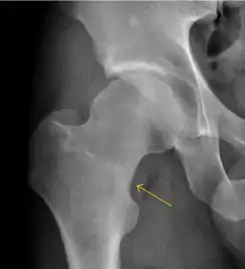

Stress femoral neck fracture in a young athlete barely visible in X-ray film as a sclerotic line (arrow)[1]

In this case, Tc 99 scintigraphy shows a band of uptake[1]

Furthermore, T1 (left) and DP fat saturated (right) weighted MR images showed the fracture line and a pattern of edema.[1]